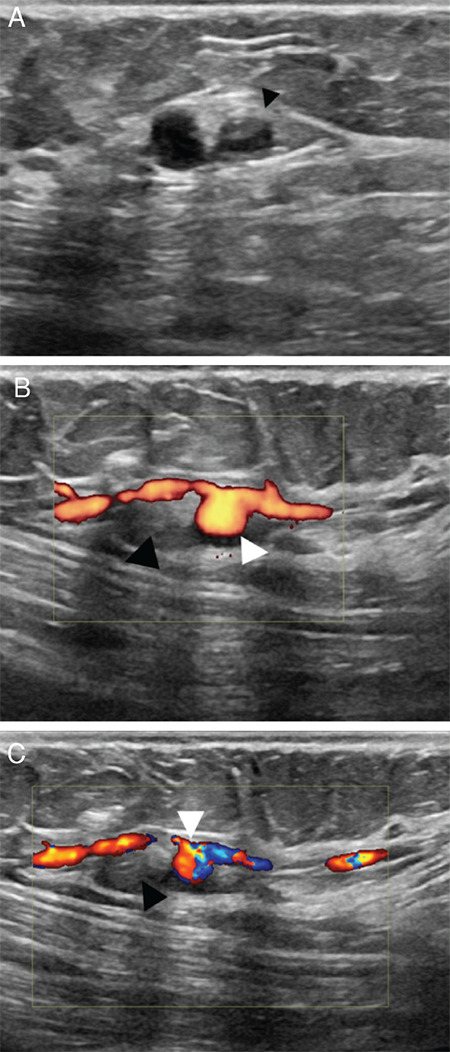

We present the case of a forty-year-old asymptomatic female with no personal or family history of breast cancer, who underwent a core needle biopsy (CNB) following the identification of a focal asymmetry in the right breast on screening mammography. Eight months later, a prominent adjacent vascular structure with a round outpouching was detected on breast ultrasound, confirmed as a post-biopsy pseudoaneurysm. Breast pseudoaneurysms, although exceedingly rare, result from inadvertent vessel puncture during core needle biopsies, particularly when larger gauge needles are used. They present as palpable, throbbing lumps in the breast and are well-defined heterogeneous structures that exhibit turbulent flow with a feeding artery on color Doppler imaging. This swirling sign showing a to-and-fro waveform is also known as the "yin-yang" sign on Doppler ultrasound. Post-CNB pseudoaneurysms in the breast, while rare, should be considered as potential complications following core need biopsy. Understanding their characteristic imaging features, risk factors, and available management options is essential for early diagnosis and appropriate treatment. This case underscores the importance of vigilance in biopsy procedures and the need for prompt recognition and intervention in case of such complications.

本病例是一名四十岁的无症状女性,无个人或家族乳腺癌病史,在乳房 X 光筛查中发现右侧乳房有局灶性不对称,随后接受了核心针活检(CNB)。八个月后,她在乳腺超声波检查中发现了一个突出的邻近血管结构,并伴有圆形外囊,证实为活检后假性动脉瘤。乳腺假性动脉瘤虽然极为罕见,但却是在核心针活检过程中不慎刺穿血管造成的,尤其是在使用较大规格的针头时。乳房假性动脉瘤表现为乳房内可触及的搏动性肿块,是界限清晰的异质结构,在彩色多普勒成像中表现为进血动脉的湍流。在多普勒超声检查中,这种显示往返波形的漩涡征也被称为 "阴阳 "征。乳腺核芯穿刺活检后假性动脉瘤虽然罕见,但应被视为核芯穿刺活检后的潜在并发症。了解假性动脉瘤的影像学特征、风险因素和可用的治疗方案对于早期诊断和适当治疗至关重要。本病例强调了在活检过程中保持警惕的重要性,以及在出现此类并发症时及时识别和干预的必要性。